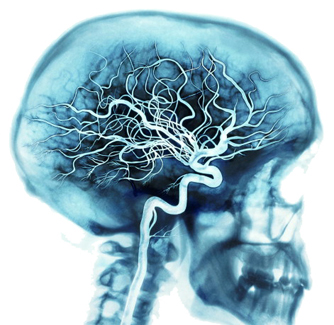

2. Linije snabdjevanja

Va� mozak se snabdjeva putem jedne od najbogatijih mre�a krvnih sudova va�eg tijela.

Sa svakim otkucajem srca, arterije prenose oko 20 do 25 procenata va�e krvi do va�eg mozga, gdje bilioni ćelija koriste oko 20 procenata kiseonika i goriva kojeg prenosi va�a krv.

Kada jako mislite, va� mozak iskoristi i do 50 procenata od goriva i kiseonika.

Cijela mre�a sudova pored arterija uključuje i vene i kapilare.